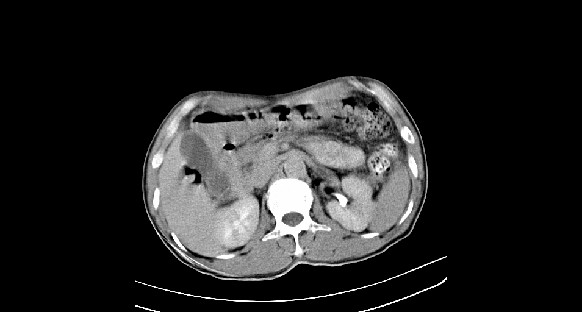

男性,70岁,体检b超发现左肾占位,请各位战友发表一下观点

左肾有两个病灶,且较大的病灶内可见点状钙化灶,增强扫描边缘也是呈渐进性强化,中央部分未见明显强化